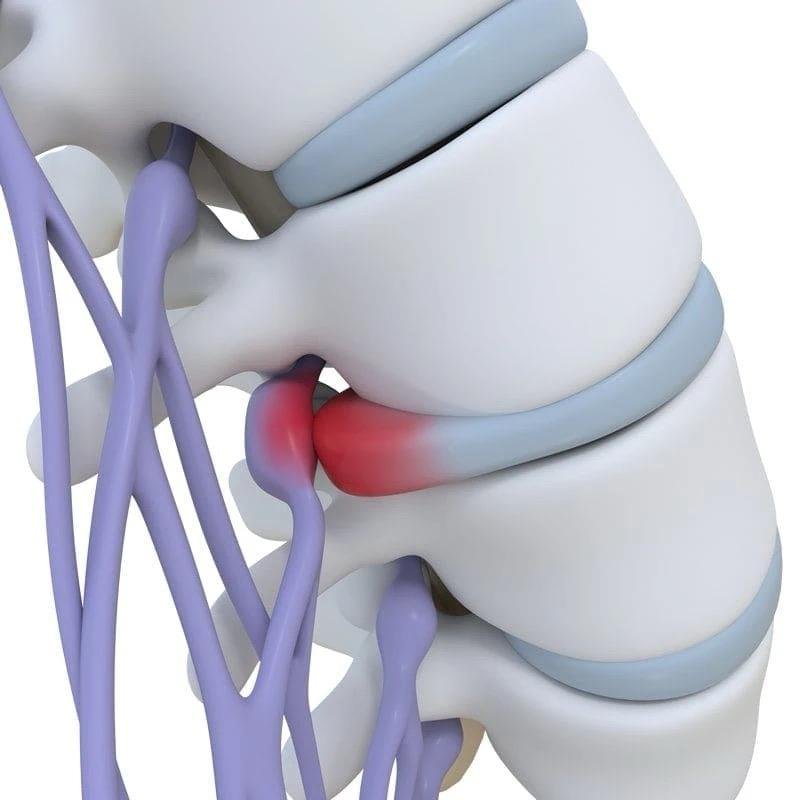

El abombamiento discal es una deformación del disco intervertebral que se desplaza o se rompe parcialmente creando un abultamiento que sobresale hacia el canal espinal. Aunque puede presentarse en cualquier parte de la columna, es más frecuente en la columna lumbar, especialmente en los niveles L4-L5, debido a la gran carga mecánica que soporta esta zona.

Protrusión discal

Es el abombamiento de las fibras periféricas del disco (anillo fibroso) hacia el canal por el que discurren las raíces nerviosas.